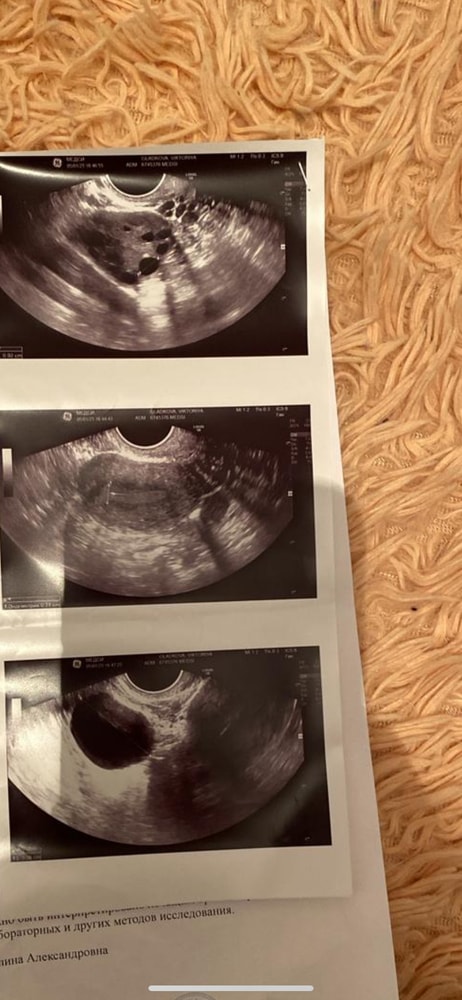

С множ. фолл. до 6 мм. лоцируется киста на ножке размером 33х30 мм.Левый яичник

Положение: типичное. Контур: четкий, ровный.

Размеры: длина: 39 мм, толщина: 24 мм, ширина: 36 мм, объем: 17.5 мл; Фолликулы: не выявлены.